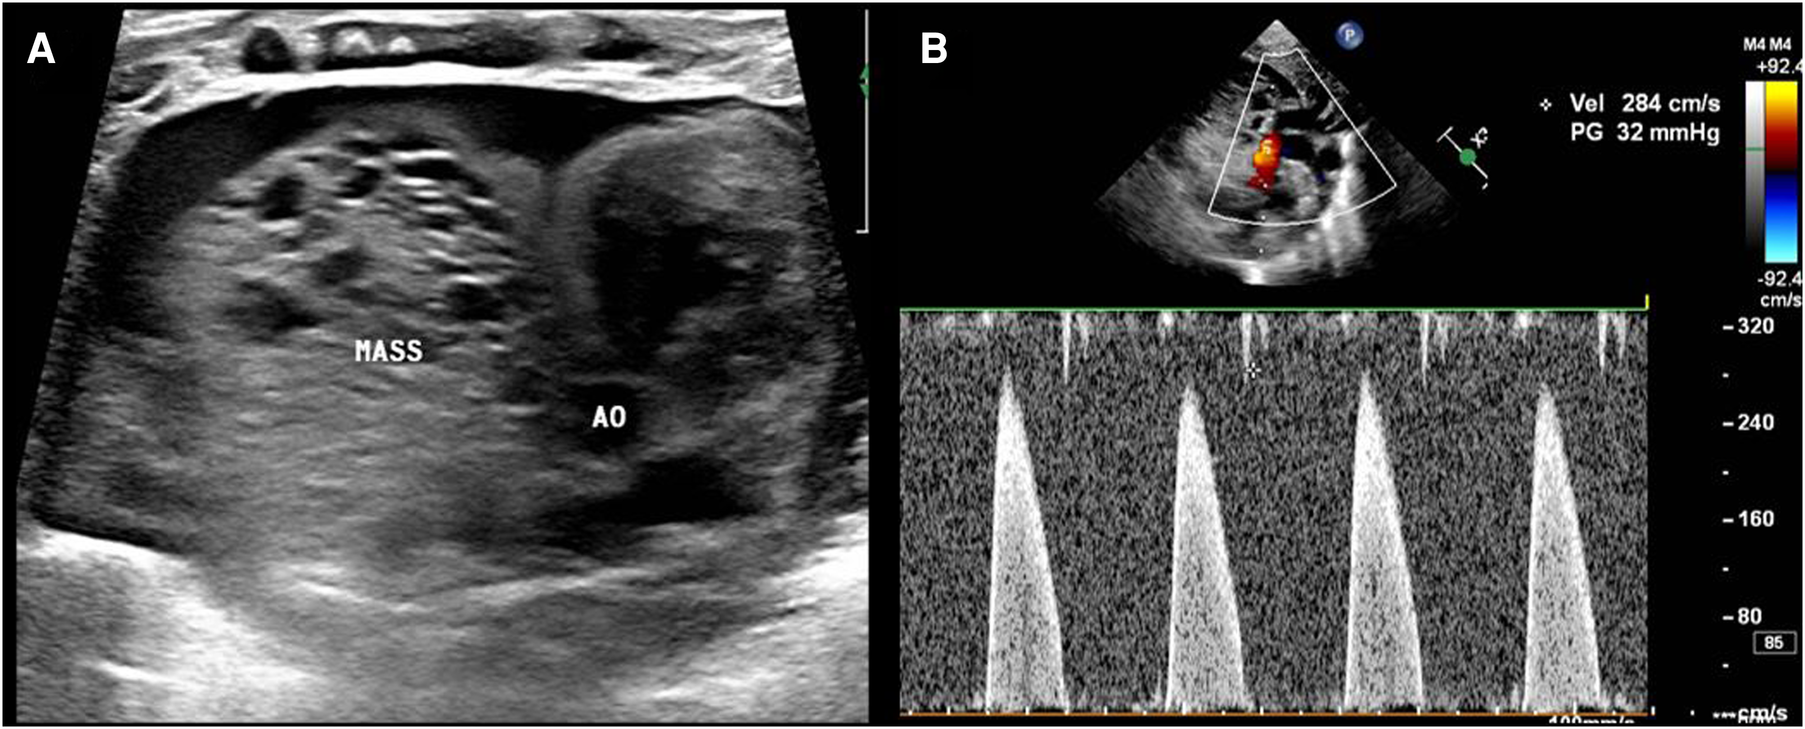

Transthoracic echocardiography (TTE) showed a slightly hyperechoic mass in the right pericardial cavity, approximately 40 × 37 mm in size (Figure 2). The mass was close to the bottom of the heart and was compressing the ascending aorta, with a clear boundary and uneven echo. Patent ductus arteriosus and atrial septal left-to-right small shunts were also observed. For better evaluation and confirmation of the diagnosis, cardiac computed tomography angiography (CTA) was performed, and a slightly low-density mass was seen outside the right atrium, with a size of approximately 44.3 × 39.2 × 42.3 mm (Figure 3). High-density strip calcifications were observed at the edge of the mass. There was an unclear boundary and mild enhancement of the lesion. There were multiple small blood vessel shadows inside, with blood supply originating from the ascending aorta (approximately 1.0 mm in diameter); the ascending aorta was evidently compressed and flattened, the heart was displaced to the left, and a large amount of pericardial effusion was seen. Chest CT scan revealed neonatal pneumonia.

Figure 2

Postnatal ultrasound images. (A) The mass (MASS) is close to the ascending aorta (AO), and the boundary is not clear. (B) The mass compresses the ascending aorta, and the velocity in the ascending aorta reaches approximately 2.8 m/s.